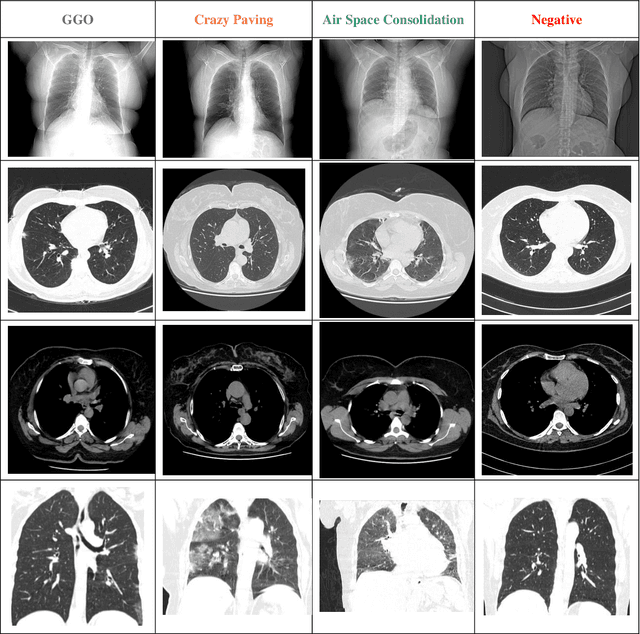

Abstract:During the COVID-19 pandemic, computed tomography (CT) is a good way to diagnose COVID-19 patients. HRCT (High-Resolution Computed Tomography) is a form of computed tomography that uses advanced methods to improve image resolution. Publicly accessible COVID-19 CT image datasets are very difficult to come by due to privacy concerns, which impedes the study and development of AI-powered COVID-19 diagnostic algorithms based on CT images. To address this problem, we have introduced HRCTv1-COVID-19, a new COVID-19 high resolution chest CT Scan image dataset that includes not only COVID-19 cases of Ground Glass Opacity (GGO), Crazy Paving, and Air Space Consolidation, but also CT images of cases with negative COVID-19. The HRCTv1-COVID-19 dataset, which includes slice-level, and patient-level labels, has the potential to aid COVID-19 research, especially for diagnosis and differentiation using artificial intelligence algorithms, machine learning and deep learning methods. This dataset is accessible through web at: http://databiox.com and includes 181,106 chest HRCT images from 395 patients with four labels: GGO, Crazy Paving, Air Space Consolidation and Negative. Keywords- Dataset, COVID-19, CT-Scan, Computed Tomography, Medical Imaging, Chest Image.